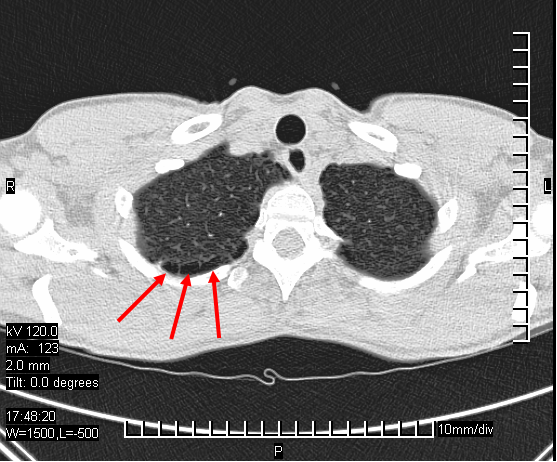

Bei der Suche nach der Ursache wurde auf einem

Röntgenbild der Lunge ein etwa 5 cm großer Hohlraum im linken oberen Lungenlappen

festgestellt, der am ehesten einem Lungenabszess entsprach. Das Blutbild war unauffällig, MRT des

Runder Hohlraum im linken oberen Lungenlappen.